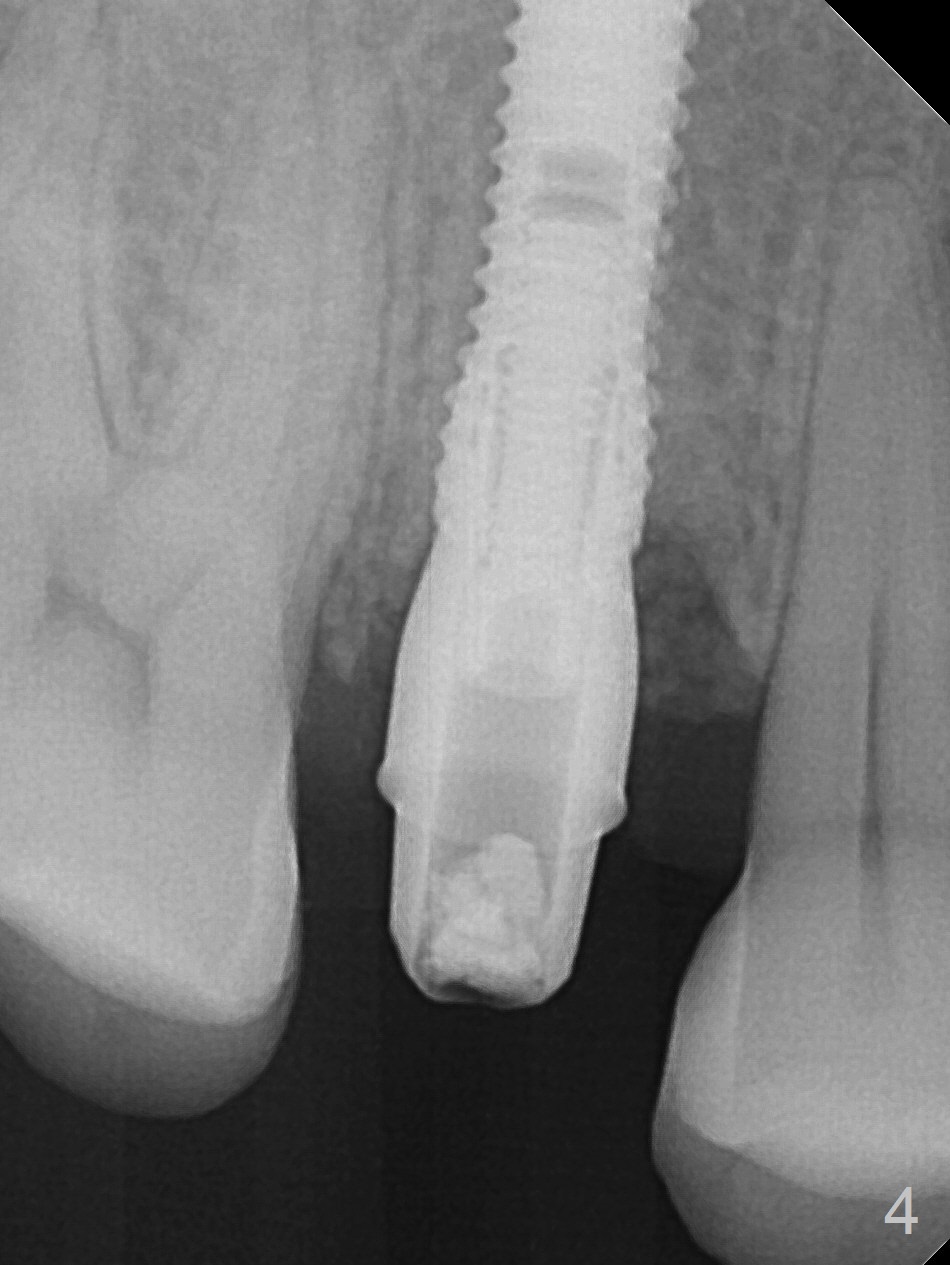

After extraction of residual root at #4 with mesiopalatal subgingival margin (Fig.1), the mesiopalatal crestal bone loss is noted. Instead of the mesial slope, the initial point of the osteotomy is at the mesial and middle (buccopalatally) of the socket bottom (Fig.2, 2'). The initial depth with 2 mm drill is 20 mm (gingival level), while the last drill (3 mm) is used for 17 mm (because of soft bone). When a 3.8x16 mm implant is placed (Fig.3,4), the distal gap of the socket is closed, suggesting that the implant moves to the least resistant area. However, it is favorable to the mesial crestal defect (Fig.4). The buccopalatal position of the abutment (4.5x4(4) mm) is a little too palatal (Fig.5, taken prior to provisional fabrication). The implant seems to have osteointegrated 6 months postop (Fig.6).